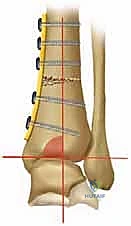

التخطيط الجراحي: دقة المليمتر مع الدكتور محمد هطيف

النجاح في جراحة قطع العظم لا يحدث في غرفة العمليات، بل في مرحلة التخطيط التي تسبقها. يستخدم الدكتور هطيف برمجيات حاسوبية متقدمة لتحليل صور الأشعة وحساب زوايا التصحيح المطلوبة بدقة متناهية.